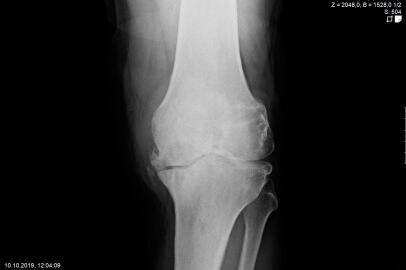

Endoprosthetics of the knee joint is an effective procedure for the treatment of symptomatic advanced wear and tear of the knee joint (gonarthrosis). If the X-ray shows a complete loss of joint space width under load, the complaints persist for more than 6 months, and the conservative therapy options have been exhausted, there is probably an indication for treatment with an artificial joint replacement (endoprosthesis). It must then be clarified which type of prosthesis is required, because today we have a large number of implants available. We distinguish between partial joints and full prostheses, and in the case of full prostheses we again distinguish between the degree of coupling of the prosthesis. If only parts of the joint are affected, only these have to be replaced and partial joints can be used. The so-called sled prostheses on the inner and outer side of the knee joint, as well as the sliding bearing replacement for problems on the kneecap, have both proven themselves effective. With full prostheses, we again differentiate between the degree of coupling of the prosthesis. Anterior and posterior cruciate ligament-supporting prostheses (surface replacement) partially coupled implants that support the inner and outer ligaments and coupled implants for complete loss of knee ligament and capsular function are used. Partially and fully coupled prostheses usually have to be inserted with stem components.